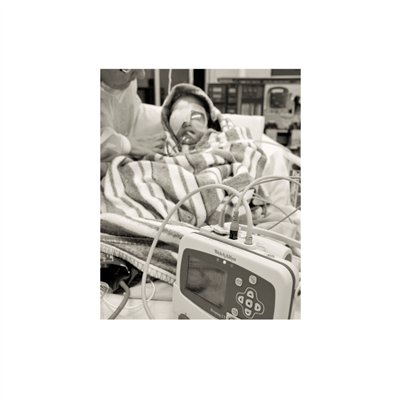

Darkness into the Light. In 2012, The Amazon Project gave eye care to nearly 6000 patients within a 200 kilometer radius of their base in Leticia, Colombia.